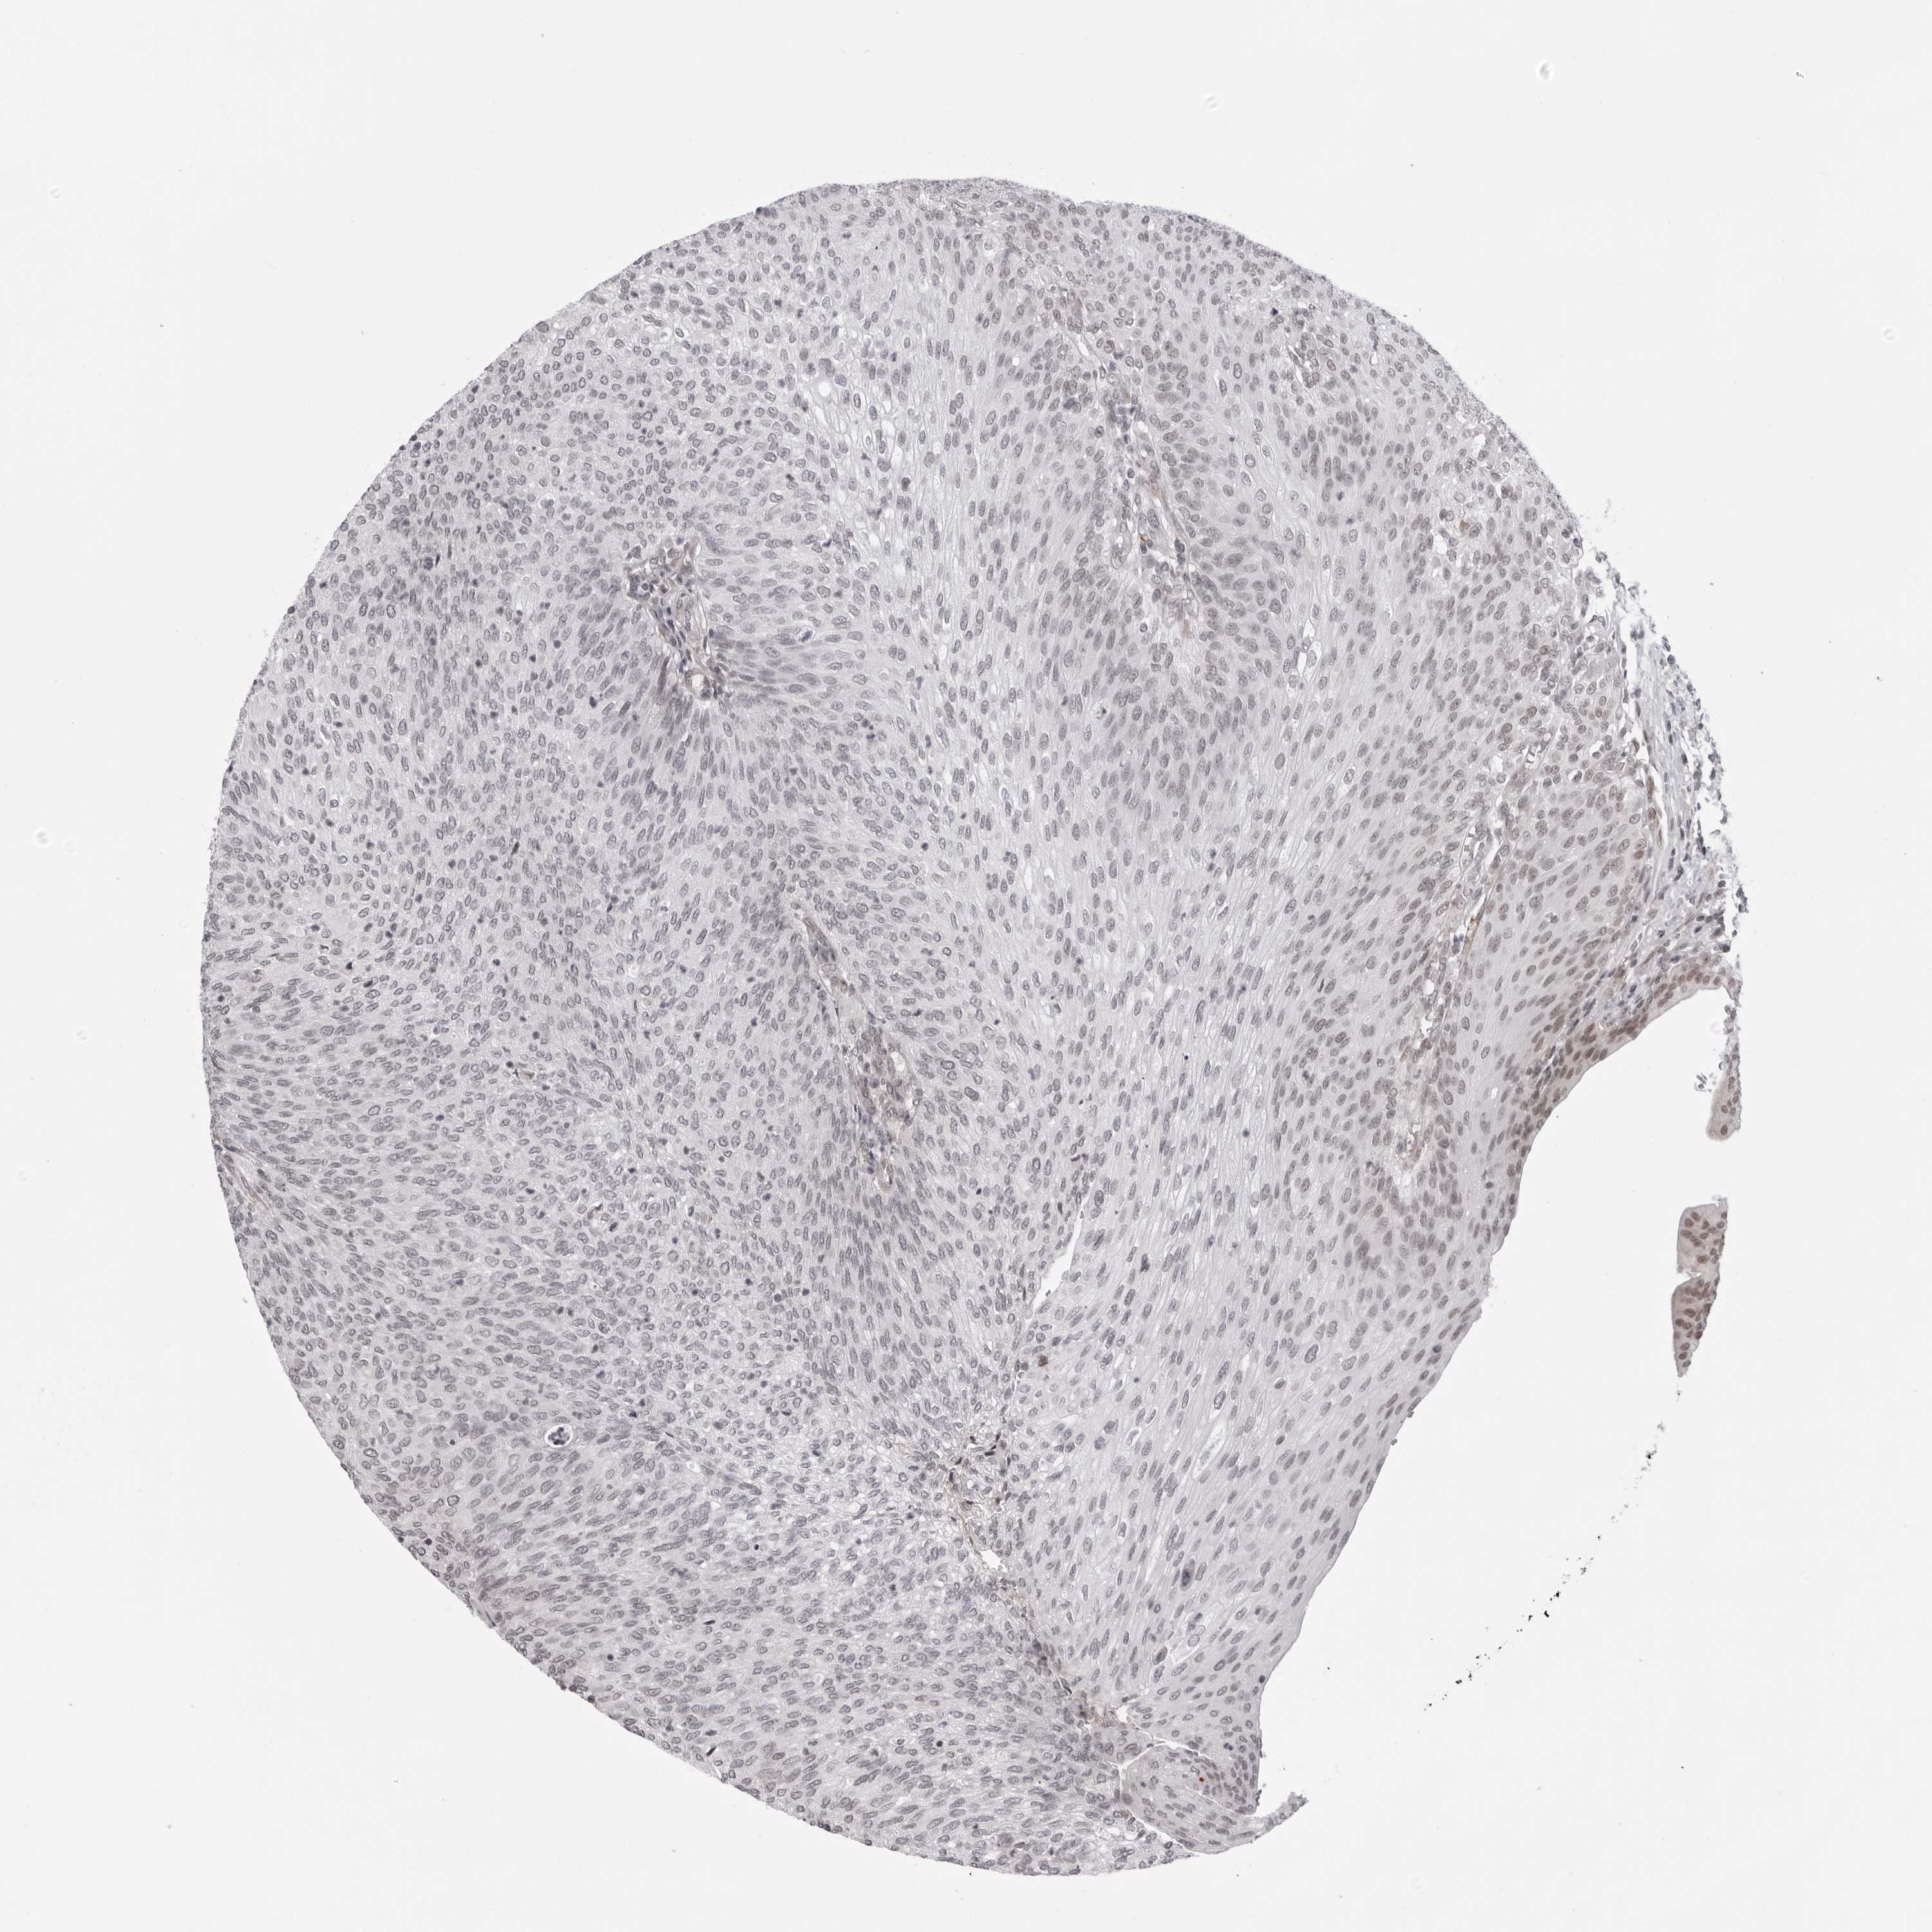

UROTHELIAL CANCER - Protein expressioni

A mouse-over function shows sample information and annotation data. Click on an image to view it in a full screen mode. Samples can be filtered based on level of antibody staining by selecting one or several of the following categories: high, medium, low and not detected. The assay and annotation is described here.

Note that samples used for immunohistochemistry by the Human Protein Atlas do not correspond to samples in the TCGA dataset.

Antibody stainingi

Antibody staining in the annotated cell types in the current human tissue is reported as not detected, low, medium, or high, based on conventional immunohistochemistry profiling in selected tissues. This score is based on the combination of the staining intensity and fraction of stained cells.

Each image is clickable and will lead to virtual microscopy that enables deeper exploration of all samples and also displays staining intensity scores, fraction scores and subcellular localization as well as patient and tissue information for each sample.

Antibody HPA024676

Antibody HPA025763

Staining

High

Medium

Low

Not detected

Intensity

Strong

Moderate

Weak

Negative

Quantity

>75%

75%-25%

<25%

None

Location

Nuclear

Cytoplasmic/membranous

Cytoplasmic/membranous,nuclear

Urothelial carcinoma, Low grade

Urothelial carcinoma, High grade